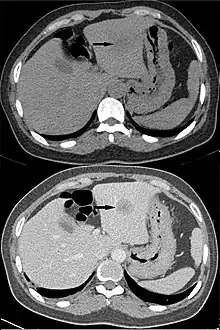

Les volumes radio-opaques ont une apparence blanche sur une radiographie, contrairement à l'apparence plus sombre des volumes radiotransparents. Par exemple, sur la radiographie standard, les os apparaissent blancs ou gris clair (radio-opaques), alors que les muscles et la peau semblent gris foncé, voire noirs ou invisibles comme les poumons, remplis d'air (radiotransparents). Les deux principaux facteurs qui contribuent à la radio-opacité d'un matériau sont sa densité et son numéro atomique.

Bien que le terme radio-opacité soit plus couramment utilisé dans un contexte de comparaison qualitative, la radiodensité peut également être quantifiée selon l'échelle de Hounsfield. Sur cette échelle, l'eau distillée a une valeur de 0 UH (Unités Hounsfield). L'air vaut −1 000 UH, tandis que les os ont des densités supérieures à 700 UH.

La radiographie a été révolutionnée par l'apparition d'agents de contraste radiodenses, qui peuvent être injectés dans la circulation sanguine, l'appareil digestif, ou le liquide céphalo-rachidien. Ils sont utilisés pour mettre en évidence certaines structures biologiques ou certains organes, notamment en tomodensitométrie (scanner). Deux produits de contraste radiodenses couramment utilisés en imagerie médicale sont le baryum et l'iode.